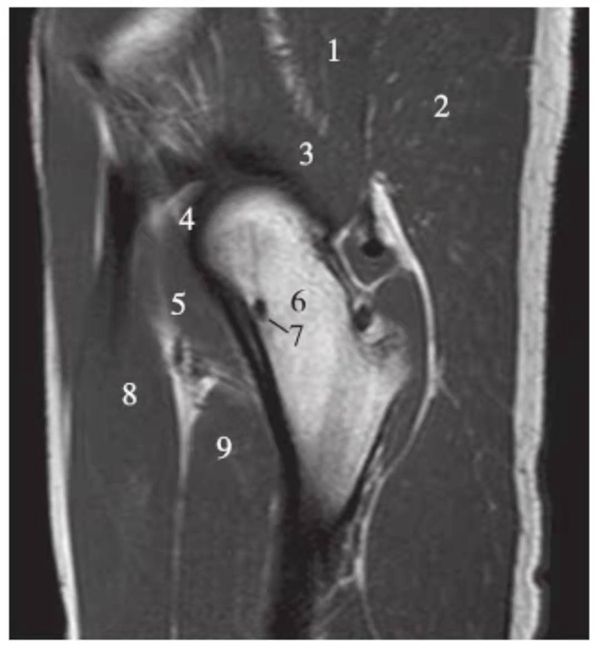

矢状位

正常髋关节经股骨头内缘层面T1WI像

1.髂骨;2.臀大肌;3.圆韧带;4.股骨头;5.坐骨;6.闭孔外肌;7.耻骨肌;8.大收肌

正常髋关节经股骨头中心层面T1WI像

1.臀中肌;2.髂骨;3.臀大肌;4.髂腰肌;5.股骨头骺线;6.股骨头;7.髋臼后唇;8.梨状肌;9.关节囊及髂股韧带;10.闭孔内肌;11.股方肌;12.大收肌